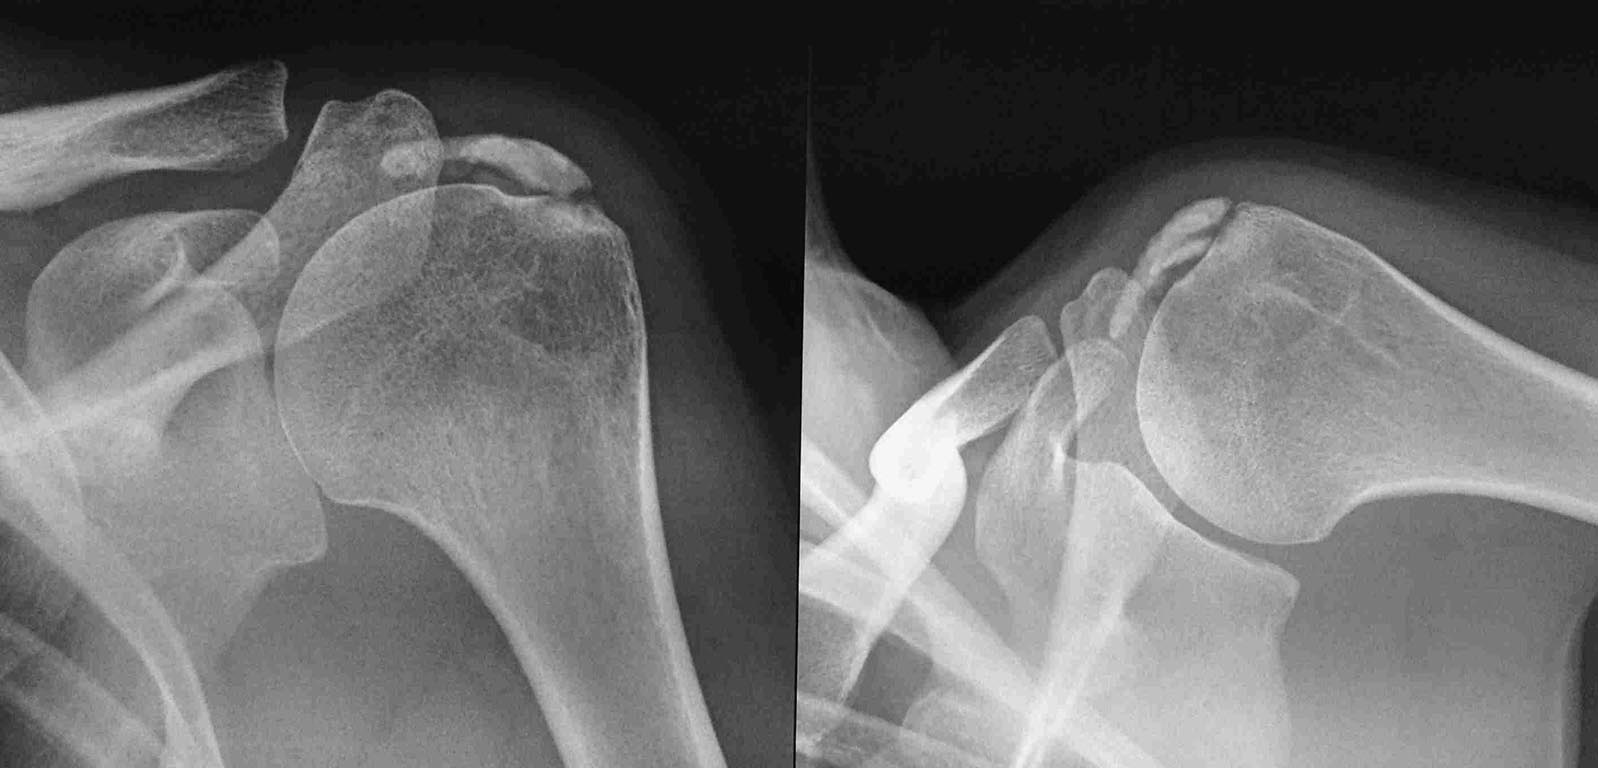

Здравствуйте уважаемые коллеги. вот возник вопрос. больная Е 36 лет кальцинирующий тендинит с обеих сторон ( на рентгенограммах одна сторона). плотность по КТ 1400.